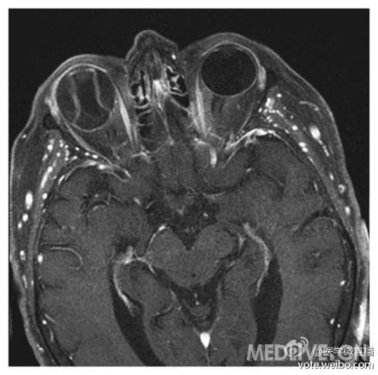

1.根据磁共振检查,其可能的诊断是什么?

A.Graves'眼病

B.视网膜剥离

C.脉络膜黑色素瘤

D.眼内移植物

E.闭角型青光眼

答案:视网膜剥离。磁共振成像显示右眼可见视网膜剥离,对称隆起异常。